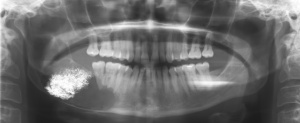

Im Jahr 2013 stellte sich nach Zuweisung durch einen niedergelassenen MKG-Chirurgen eine 44jährige Patientin in der Ambulanz für MKG-Chirurgie des Bundeswehrkrankenhauses Hamburg vor. Anamnestisch bestand seit etwa drei Jahren ein Druck- und Schmerzempfinden im Bereich des rechten Kieferwinkels sowie der rechten Unterkieferseitenzähne. Daraufhin wiederholt durch den Hauszahnarzt angefertigte Bissflügel- und Einzelzahnaufnahmen hatten keinen pathologischen Befund erbracht. Erst als die Patientin auf Grund der persistierenden Beschwerden zu einem MKG-Chirurgen überwiesen worden war, wurde in einer Panoramaschichtaufnahme eine großvolumige Zyste im Bereich des rechten Unterkieferwinkels entdeckt (Abbildung 5).

Die durch den zuweisenden Kollegen entnommene Probe erbrachte die Diagnose eines keratozystischen odontogenen Tumors. Die extraorale Untersuchung bei der stationären Aufnahme war unauffällig, der intraorale Befund ergab ein karies- und füllungsfreies Gebiss. Die ergänzend angefertigte Computertomographie des Unterkiefers zeigte eine von der Basis des Unterkiefercollums bis distal des Zahnes 44 reichende Zyste (Abbildungen 6 und 7).

Da der die Zyste begrenzende Knochen teils extrem ausgedünnt war, erfolgten eine Unterkieferteilresektion und im gleichen Eingriff die Rekonstruktion mit einem mikrochirurgisch reanastomosierten Beckenkammtransplantat (Abbildung 8).